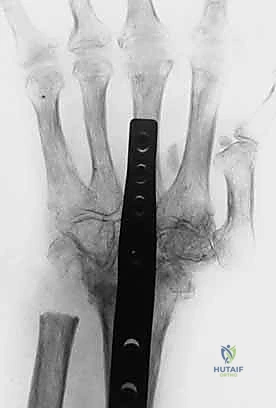

- التصوير الشعاعي (X-Rays):

- ضروري جداً لاستبعاد وجود كسور قلاعية (Avulsion Fractures) حيث ينفصل الوتر آخذاً معه قطعة من العظم، وكذلك لتقييم درجة تلف الغضاريف بسبب الروماتويد.

2. التدخل الجراحي المتقدم (خبرة الأستاذ الدكتور محمد هطيف)

عندما يفشل العلاج التحفظي، أو إذا كان التشوه ثابتاً ومتيبساً، أو في حالات الروماتويد المتقدمة، يصبح التدخل الجراحي حتمياً لاستعادة وظيفة اليد. يُعد الدكتور هطيف رائد عمليات جراحة اليد الميكروسكوبية في اليمن، ويستخدم تقنيات حديثة تضمن أعلى نسب النجاح.

ج) جراحات المفاصل المتقدمة (للتشوهات المتيبسة والروماتويد):

- استبدال المفصل (Arthroplasty): تغيير مفصل الإصبع التالف بمفصل صناعي لاستعادة الحركة وتخفيف الألم.

- دمج المفصل (Arthrodesis): في الحالات الشديدة جداً، يتم تثبيت المفصل في وضع وظيفي (شبه منثني) لإزالة الألم بشكل نهائي وتوفير قبضة قوية، وإن كان ذلك على حساب حركة المفصل المدمج.